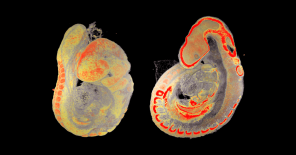

The phenotyping module at the Czech Center for Phenogenomics houses a comprehensive collection of tools for the physiological and morphological assessment of experimental mice and rats in a controlled SPF (specific pathogen-free) environment. Our mission is to support the preclinical research and development community with service of the highest professional standard. More info

Our experienced staff offers a wide variety of standardized tests and services, including those of IMPReSS (International Mouse Phenotyping Resource of Standardised Screens), mandated by our active partnership in the International Mouse Phenotyping Consortium. Notable is our capacity for conducting comprehensive phenotyping pipelines, providing a wide breadth of clinical information per experimental animal, and thereby minimizing overall animal usage.